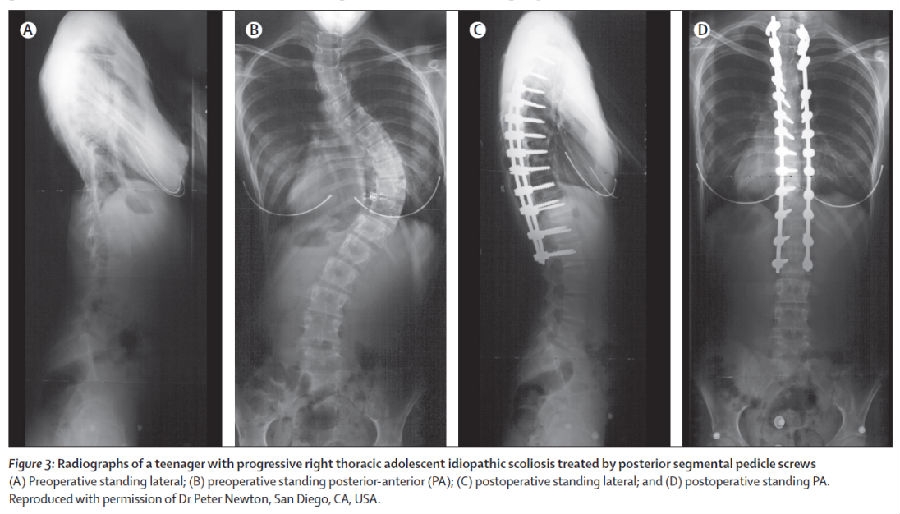

2.手术治疗

AIS冠状面主弯Cobb角大于45°是公认的手术适应症,而手术治疗的主要目的包括:1控制侧凸进展;2实现最大程度的矫形;3改善外观;4避免短期及长期并发症。在手术时机的选择上,当患者侧凸进展到达到手术标准后应建议尽快手术,推迟手术时间可能会导致固定节段延长、手术复杂性增加、并发症发生率升高等一系列问题。

手术方式方面,本篇综述发表的时候仍有较多前后路联合手术的报道;近年来随着脊柱后路矫形技术的不断进步,单纯后路一期手术足以取得理想的矫形效果。此外,术中神经电生理监测、血液回收技术等均有助于提高手术安全性。当然,脊柱矫形手术仍然是高难度的骨科手术,具有手术时间长、手术风险高、学习曲线陡峭等特点。